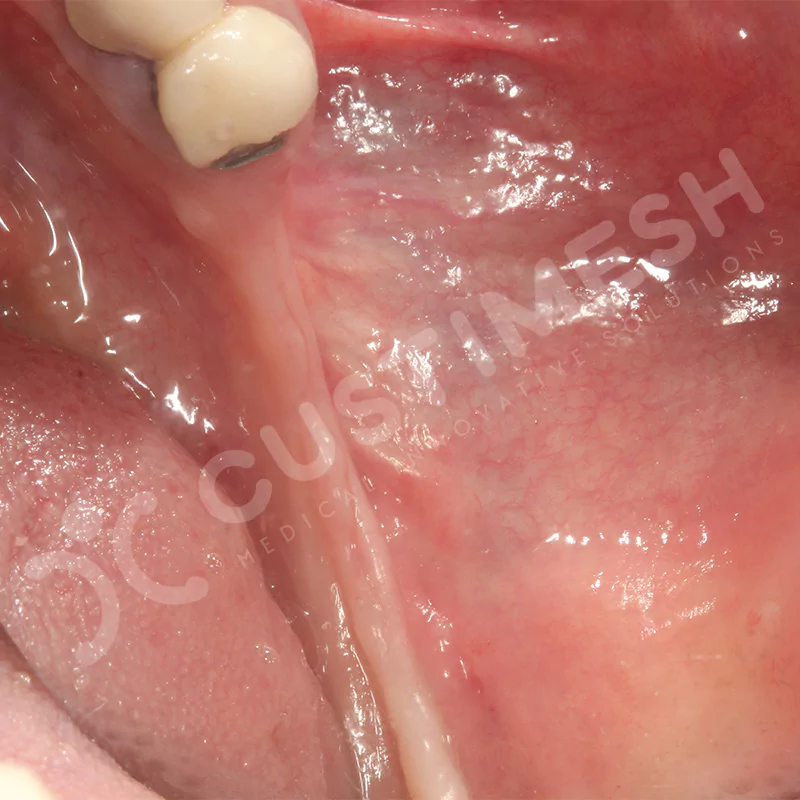

VAKA 3